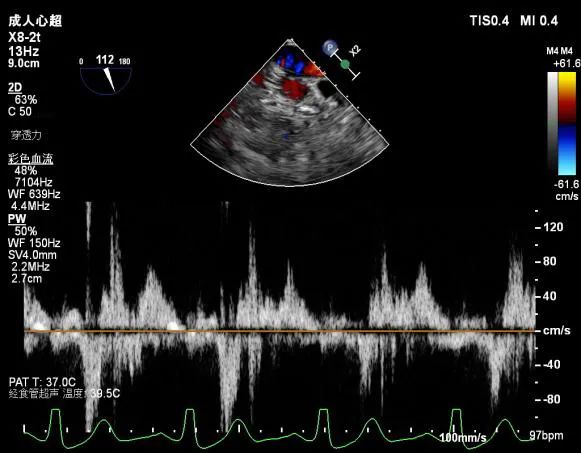

肺静脉血流频谱呈收缩期反向

肺静脉血流频谱逐渐恢复正向

肺静脉血流频谱恢复正向

肺静脉血流频谱完全正向